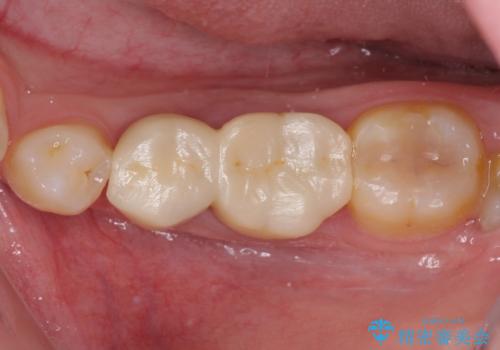

当初は歯肉が腫れ上がり、大変不快な思いをされていましたが、セラミッククラウン装着後は清掃性が著しく改善し、患者様には大変満足していただきました。